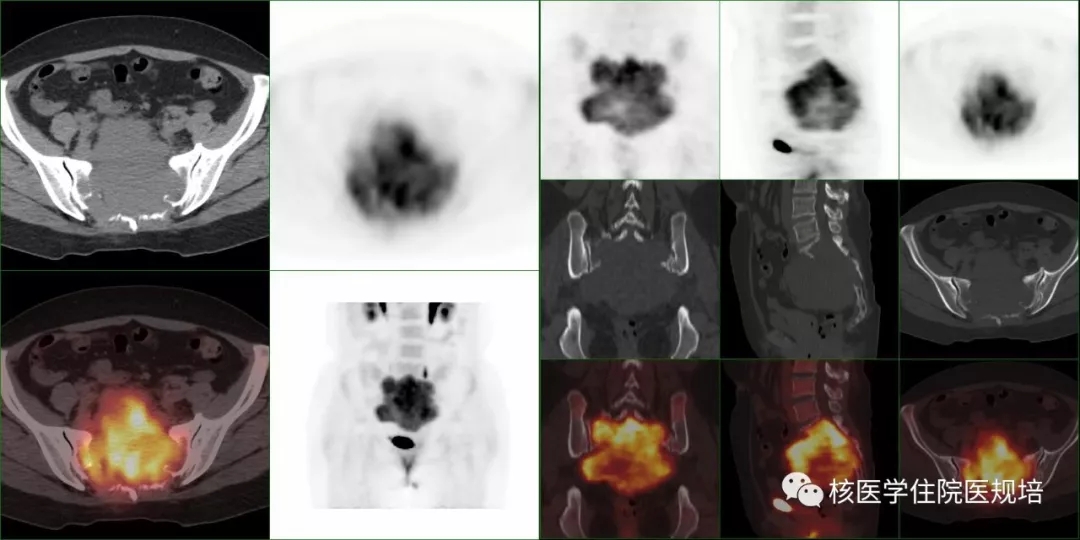

FDG-PET/CT检查所见及最终临床诊断:

静脉注射18F-FDG 60分钟后行骨盆区局部PET/CT显像,示该软组织肿物高度摄取FDGSUVmax8.8),结合骨显像,考虑骶骨肿瘤为巨细胞瘤。

3.PET/CT图像